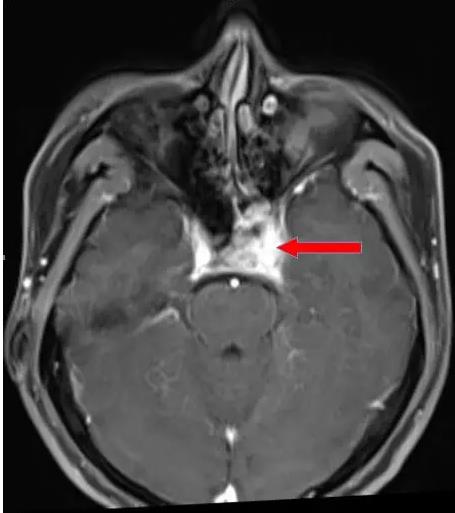

鼻咽癌海綿竇受侵影像表現

腫瘤侵犯左側海綿竇,向后累及斜坡。